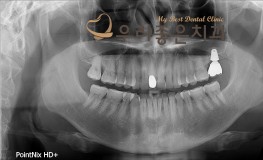

우리좋은치과 치아 상실 및 골소실 → 뼈이식 및 임플란트 보철 치료(이**2014...

No.304

임플란트

2019-07-26

1388